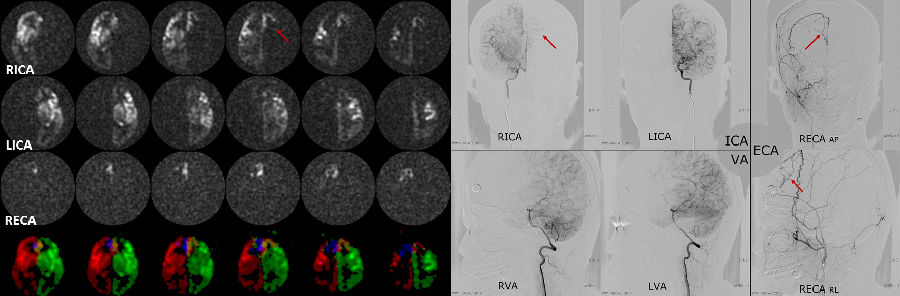

上图:选择性动脉自旋标记技术(tASL)应用于烟雾病。患者右侧颈外动脉形成代偿灌注;右侧颈内动脉于对侧形成代偿支;椎基底供血枕顶叶。tASL在烟雾病的诊断与分级中有巨大的潜在应用价值。& #40;病例取自华山医院& #41;

上图:67岁缺血性脑卒中患者,双侧大脑中动脉存在狭窄。分别进行了3D ASL(A,B)与tASL(B-D,F-H)标记。图中箭头所示为常规ASL中无异常灌注的区域,在tASL中可以看到箭头所示区域存在来自椎基底动脉的代偿供血。(病例取自苏北人民医院)

上图:69岁女性,间断头晕半年,加重两周,左侧颈总末端狭窄,12号进行颈总内膜剥脱手术。在tASL中可以观察到左右颈内动脉在手术前后灌注区域的改变。对于慢性一侧颈内动脉狭窄的病人,在建立侧枝循环的过程中,脑血管灌注会再分配,同时大部分患侧都是灌注减低。当狭窄解除后,血流灌注再次进行再分配,大部分患者都是灌注增高。这种灌注的快速变化,会导致脑过度灌注综合症。所以我们在术后进行脑组织灌注再分配显示及其定量分析就显得尤为重要。(病例取自北京协和医院) 在对脑血管类疾病供血的精细研究中,具有血管选择性的动脉自旋标记技术(Territorial ASL, tASL)因建立起了供血源与灌注区域的直接联系,往往可以发挥更大的价值。结合超选择与血管编码技术(super-selective ASL, ssASL[17];vessel-encoding ASL, veASL[18]),tASL可实现选择性地观察特定血管的供血灌注情况。这对于代偿支的灌注评估具有其他技术无可比拟的优势。 参考文献 [1] J. Detre, et al. Perfusion Imaging. MRM 1992 [2] D. Alsop, et al. Recommended Implementation of Arterial Spin Labeled Perfusion MRI for Clinical Applications: A Consensus of the ISMRM Perfusion Study Group and the European Consortium for ASL in Dementia. MRM 2014 [3] J. Wang, et al. Comparison of quantitative perfusion imaging using ASL at 1.5T and 4T. MRM 2002 [4] S. Kim. Quantitative of relative cerebral blood flow change by FAIR technique: application to functional mapping. MRM 1995 [5] E. Wang, et al. Implementation of quantitative perfusion imaging techniques for functional brain mapping using pASL. NMR Biomed 1997 [6] X. Golay, et al. PULSAR: a robust regional perfusion technique for high field imaging. MRM 2005 [7] G. Jahng, et al. Improved perfusion-weighted MRI by a novel DIPLOMA. MRM 2003 [8] R. Buxton. Introduction to Functional MRI: Principles and Techniques 2nd. 2009 [9] R. Irie, et al. Assessing Blood Flow in an Intracranial Stent: A feasibility study of MRA using a silent scan after stent-assisted coil embolization for anterior circulation aneurysms. AJNR 2015 [10] J. Wang, et al. The value of ASL perfusion imaging in acute ischemia stroke: Comparison with DSC MRI. Stroke 2012 [11] J. Boxerman, et al. Relative Cerebral Blood Volume Maps Corrected for Contrast Agent Extravasation Significantly Correlate with Glioma Tumor Grade, whereas Uncorrected Maps Do Not. [12] R. McDonald, et al. Intracranial Gadolinium Deposition after Contrast-enhanced MRI. Radiology 2015 [13] FDA: http://www.fda.gov/Drugs/DrugSafety/ucm455386 [14] Y. Li, et al. Cardiac-triggered pcASL: A cost-effective scheme to enhance the SNR of ASL. ISMRM 2015 [15] R. label. The many advantages of arterial spin labeling with long label duration. ISMRM 2015 [16] W. Dai, et al. Reduced Resolution Transit Delay Pre-scan for Quantitative Continuous Arterial Spin Labeling Perfusion Imaging. MRM 2012 [17] E. Wang. Vessel Encoded Arterial Spin-Labeling Using Pseudo-continuous Tagging. MRM 2007 [18] M. Helle, et al. Super-selective Pseudo-continuous Arterial Spin Labeling. MRM 2010